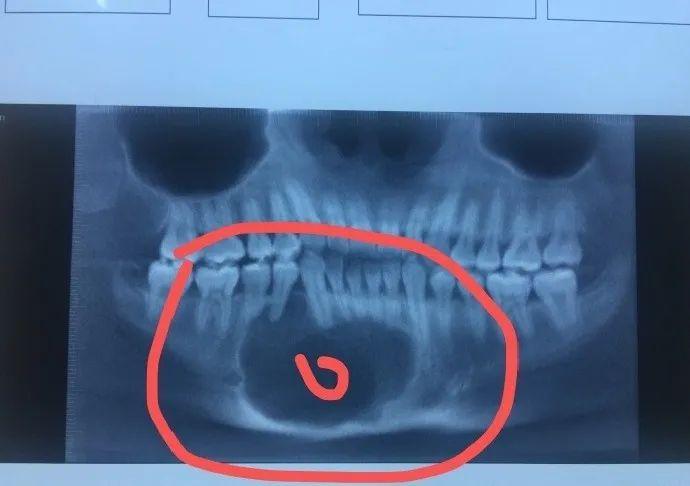

13岁的小鹏在一次例行口腔检查中,意外发现了隐藏在他颌骨内的六颗“炸弹”——双侧上颌后牙及下颌后牙含牙囊肿。这个案例揭示了一个令人警醒的事实:看似无害的颌骨囊肿,如果不及时发现和治疗,可能会带来严重的后果。

含牙囊肿的隐蔽性极高,早期往往没有任何症状。正如小鹏的案例所示,他在就诊前并未感到任何不适,直到进行全面口腔检查时才被发现。这种隐蔽性使得颌骨囊肿很容易被忽视,但其潜在危害却不容小觑。

诊断颌骨囊肿主要依靠影像学检查,如X线、CT或磁共振成像(MRI)。这些检查能够帮助医生准确判断囊肿的位置、大小和性质。在小鹏的案例中,医生正是通过详尽的CBCT检查才发现隐藏在颌骨内的多颗囊肿。